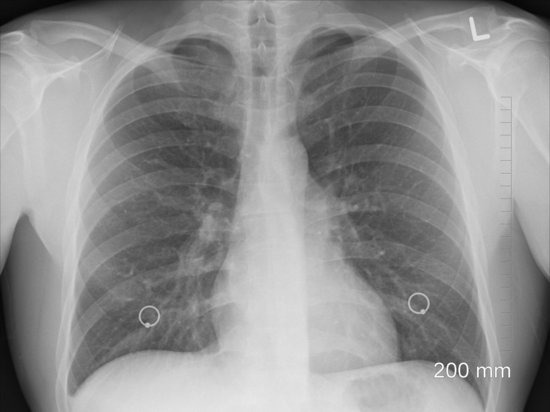

Напомним, ранее врач-патологоанатом, клинический фармаколог Александр Эдигер поделился мнением об изменениях в легких человека при поражении новым коронавирусом. Эксперт сделал выводы на основе наблюдения за больными COVID-19, а также после вскрытия скончавшихся от инфекции.

“Это никакая не пневмония", - приводит слова эксперта ИА "Общественная служба новостей". Эдигер объяснил, что воспаление легких обусловлено микробным или микробно-вирусным возбудителем или с формированием сложной ассоциации возбудителей. При этом по его словам, воспаление имеет достаточно ограниченный по времени процесс. Фатальный исход этого процесса происходит в самом крайнем случае.